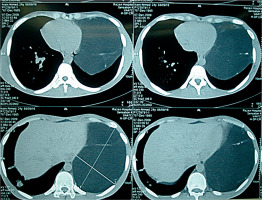

Chest computed tomography (CT) showed a large mass (22 × 19 × 17 cm) with fat density admixed with soft tissue strands occupying the anterosuperior mediastinum extending to the left hemithorax (Figure 2). Laboratory tests were not remarkable. The patient was scheduled for surgical resection with a primary diagnosis of thymolipoma. Care was taken as regards malacia or external pressure of the left main bronchus. Partial sternotomy was accompanied with left thoracotomy through the fifth left intercostals space. The tumor (31 × 15 × 12 cm) resided left of the pericardium without any invasion to pericardial or lung tissue (Figure 3). Dehiscence of the tumor by blunt and sharp dissection was easily done with care about preservation of the left phrenic nerve.

Figure 2

Chest computed tomography of the case representing huge left mass comprising fat density with strands of soft tissue density with mild compressing effect on the heart pushing it to the right